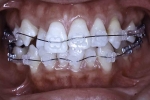

治療中

|